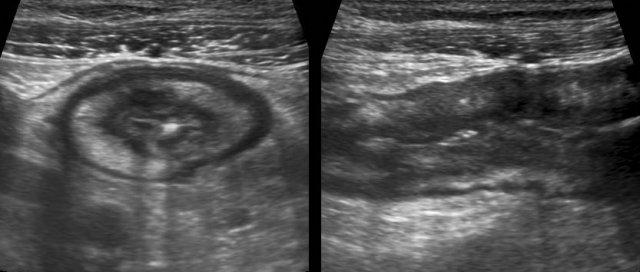

Sự khác biệt về kích thước và khả năng bị ép xẹp của hồi tràng bình thường (bên trái) và hồi tràng bị tổn thương do Crohn trong quá trình ép dần từng bước.

Sử dụng kỹ thuật ép dần từng bước, hai đoạn ruột kề nhau được ép vào cơ thắt lưng chậu.

Đoạn ruột phía trước là bình thường và dễ dàng bị ép xẹp, trong khi quai ruột bị Crohn hầu như không thể bị ép xẹp.